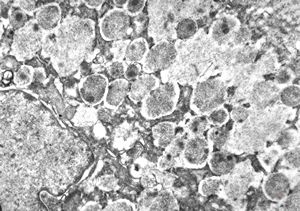

M,41y. | hairy cell leukemia - spleen - ribosome-lamella complex in tricholeukocyte